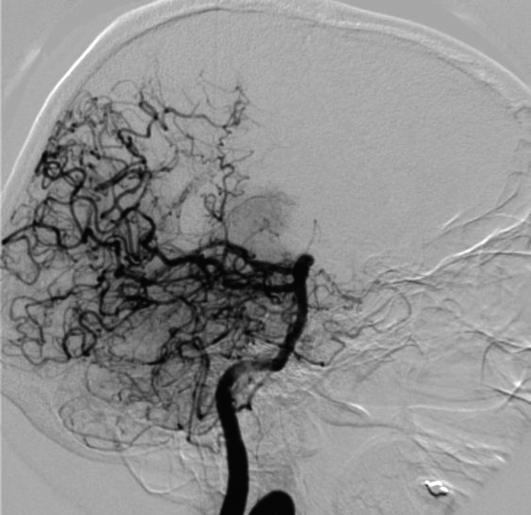

Moyamoya is een aandoening die ontstaat door vernauwing van bloedvaten die bloed naar de hersenen vervoeren. De hersenen krijgen dan te weinig bloed aangevoerd. Als gevolg daarvan groeit er een netwerk van haarvaten om de vernauwde bloedvaten heen. Op een röntgenfoto ziet dit eruit als een rookwolk. Moyamoya is een Japans woord dat 'rookwolk' betekent.